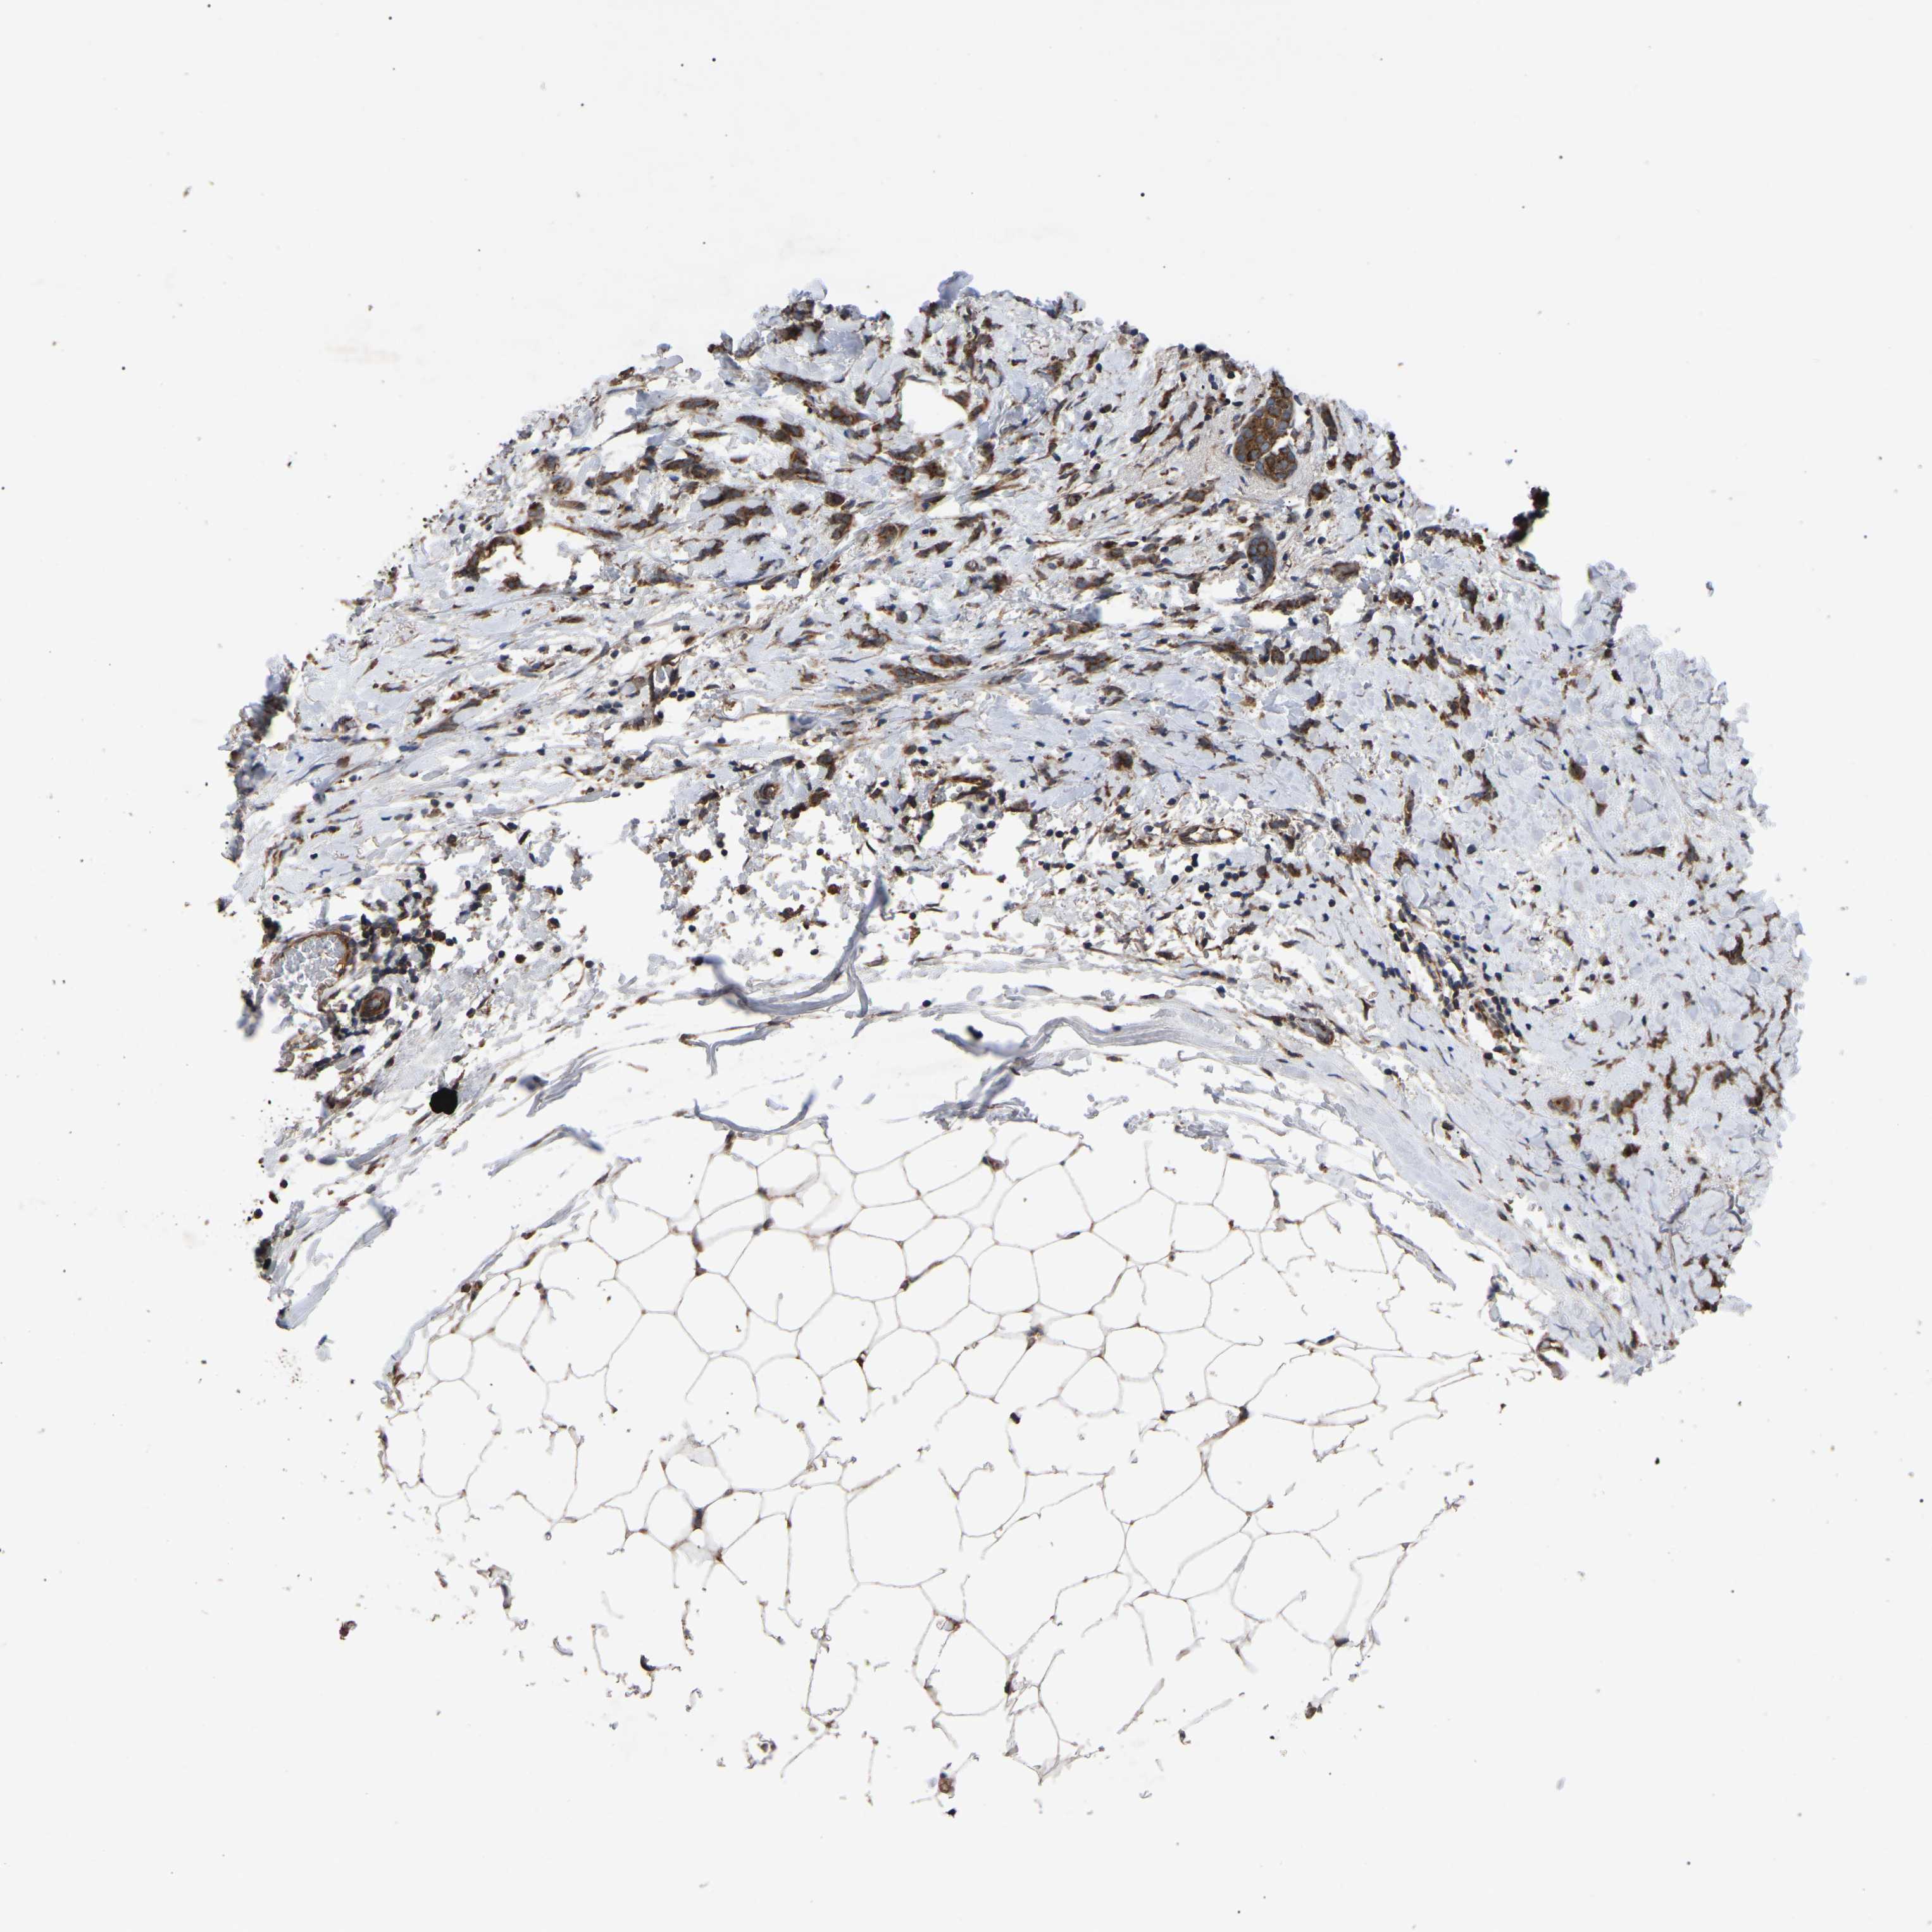

CANCER BREAST CANCER Show tissue menu

BRCA TCGA BRCA VALIDATION PROTEIN EXPRESSION